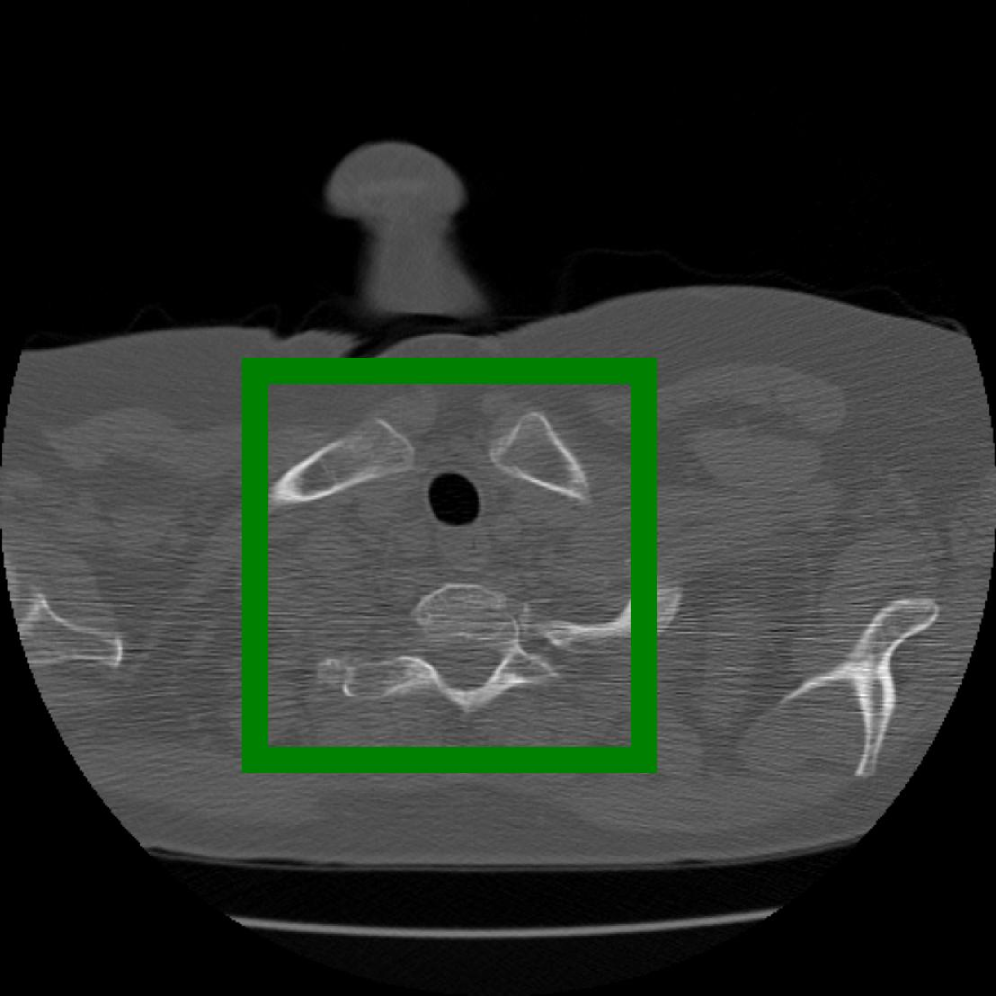

Figure 12: The visual comparison of different compression methods on another CT Heart Segmentation image.

Figure 13: Zoomed-in view of the highlighted region in Figure 12.

IV-B3 Visual Comparison

Figures 7 and 8 present representative examples from the CIL dataset and their zoomed-in regions, respectively. For the CT Heart Segmentation dataset, Figures 10 and 12 illustrate typical reconstruction results, while Figures 11 and 13 further enlarge local regions to compare structural details. Across both datasets, COLI preserves fine structures and global continuity well even at relatively low bpp. Specifically, on the CIL dataset, COLI attains the lowest bitrate among INR-based methods while still maintaining clear texture details. On the CT Heart dataset, COLI also operates at a low bpp within the INR family and delivers superior visual quality with improved detail fidelity and smoother structural presentation. The zoomed-in regions show fewer blocking artifacts and smoother transitions, making COLI especially suitable for large images and medical images. These visual results validate that INR-based compression can achieve efficient storage with reliable perceptual consistency, offering practical advantages for real-world large-scale image processing.